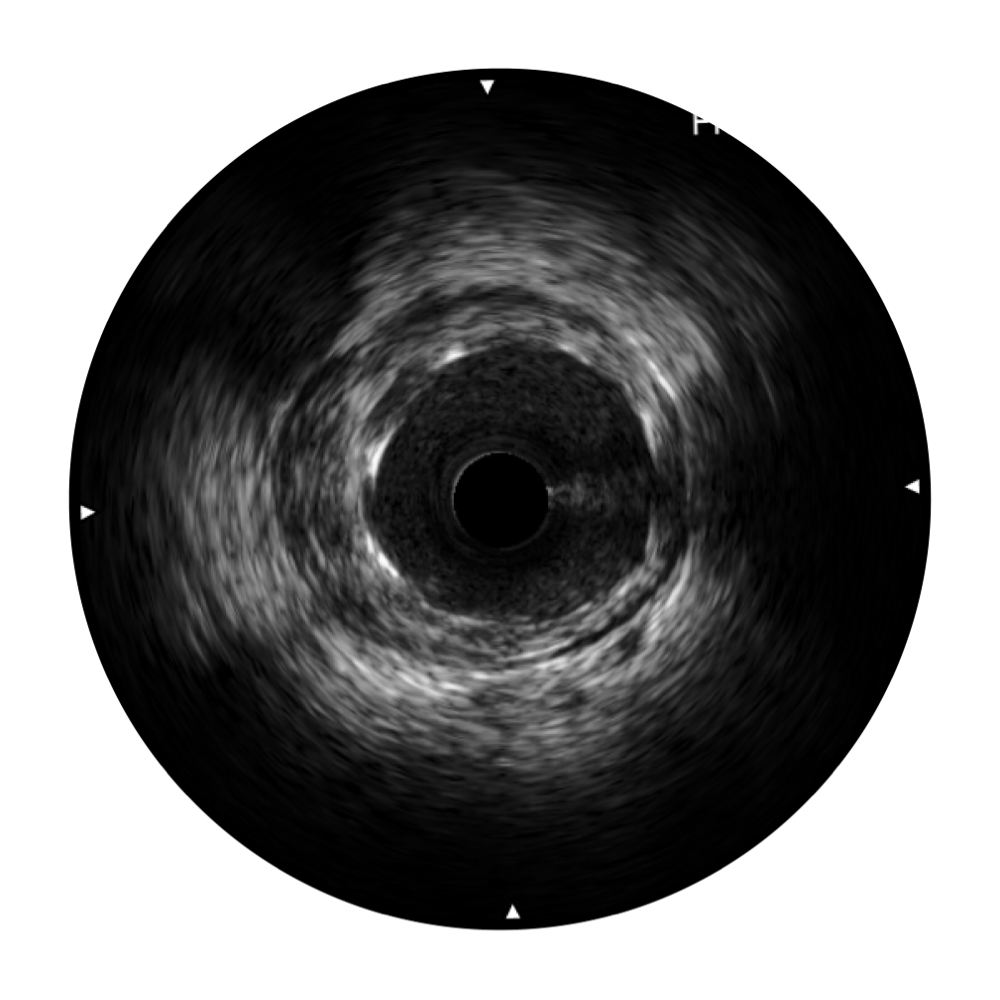

血管内超声(IVUS) 通过对病变程度、性质和累及范围的精确判断,可帮助选择治疗策略和方法,指导介入治疗过程,能够降低主要不良心血管事件,改善预后,在复杂病变介入治疗中用于指导支架置入的优势更为明显。血管内超声(IVUS)已成为精准心血管介入治疗的“金标准”。

DB中国旗舰官方网站超宽频成像技术覆盖20-80MHz1或20-90MHz2频率范围, 提供优异的分辨力同时也保证充足的穿透深度

对比传统IVUS导管成像,DB中国旗舰官方网站宽频IVUS图像的近场支架梁显影更细腻,远场中膜外血管仍清晰可辨,兼顾远中近,兼顾分辨力与穿透深度